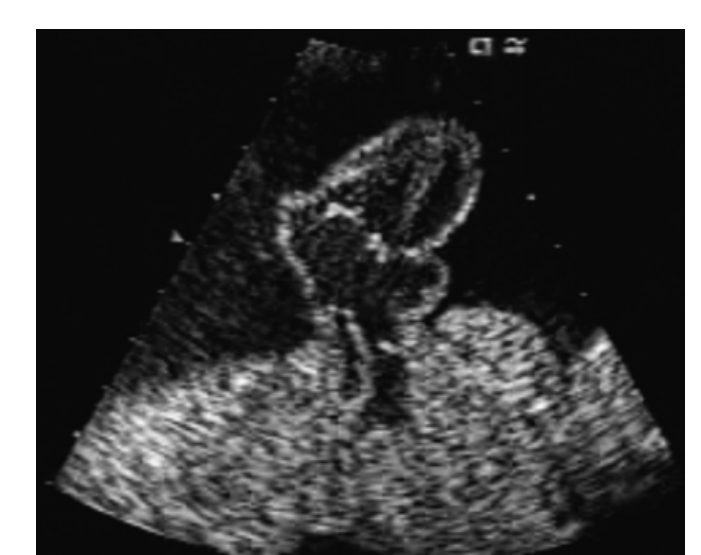

What is Ectopia Cordis?

The heart is located outside of the chest cavity

Ectopia Cordis, what number are common with which sex? and associated with what?

• 2/3rds are male •

Associated with trisomy 18

Ectopia Cordis, Described as the what?

Described as the pentalogy of Cantrell

Midline supraumbilical abdominal wall defect •

Lower sternum defect •

Deficiency of the anterior diaphragm •

Pericardial defect •

And congenital heart malformation (tetralogy of Fallot, DORV, VSD or LV diverticulum